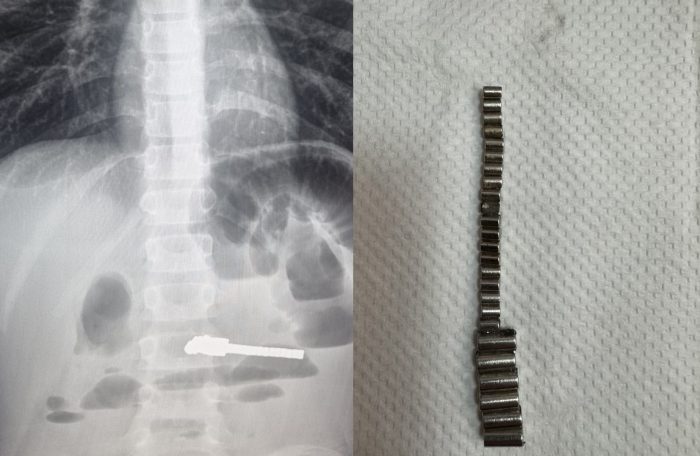

«Обследование выявило множественные рентгенконтрастные предметы в кишечнике и явные признаки кишечной непроходимости. Ребенок был экстренно прооперирован, и в ходе операции было удалено 25 магнитов. К сожалению, длительное нахождение этих предметов в ЖКТ уже привело к серьезным осложнениям: перфорации стенки желудка, тонкой кишки и образованию межкишечного свища», — говорит главврач ДГКБ №1 Евгения Аверкина.

Отмечается, что ежегодно в хирургию детской больницы госпитализируют 3-7 ребят с инородными телами в животе, но случаи с магнитами вызывают особую тревогу. Они притягиваются друг к другу через стенки кишечника, что приводит к непроходимости, некрозу тканей, перфорации (образованию отверстия в стенках желудка или кишечника в результате некроза или сильного давления) и формированию свищей (неестественных сообщений между органами), как и получилось в данном случае.